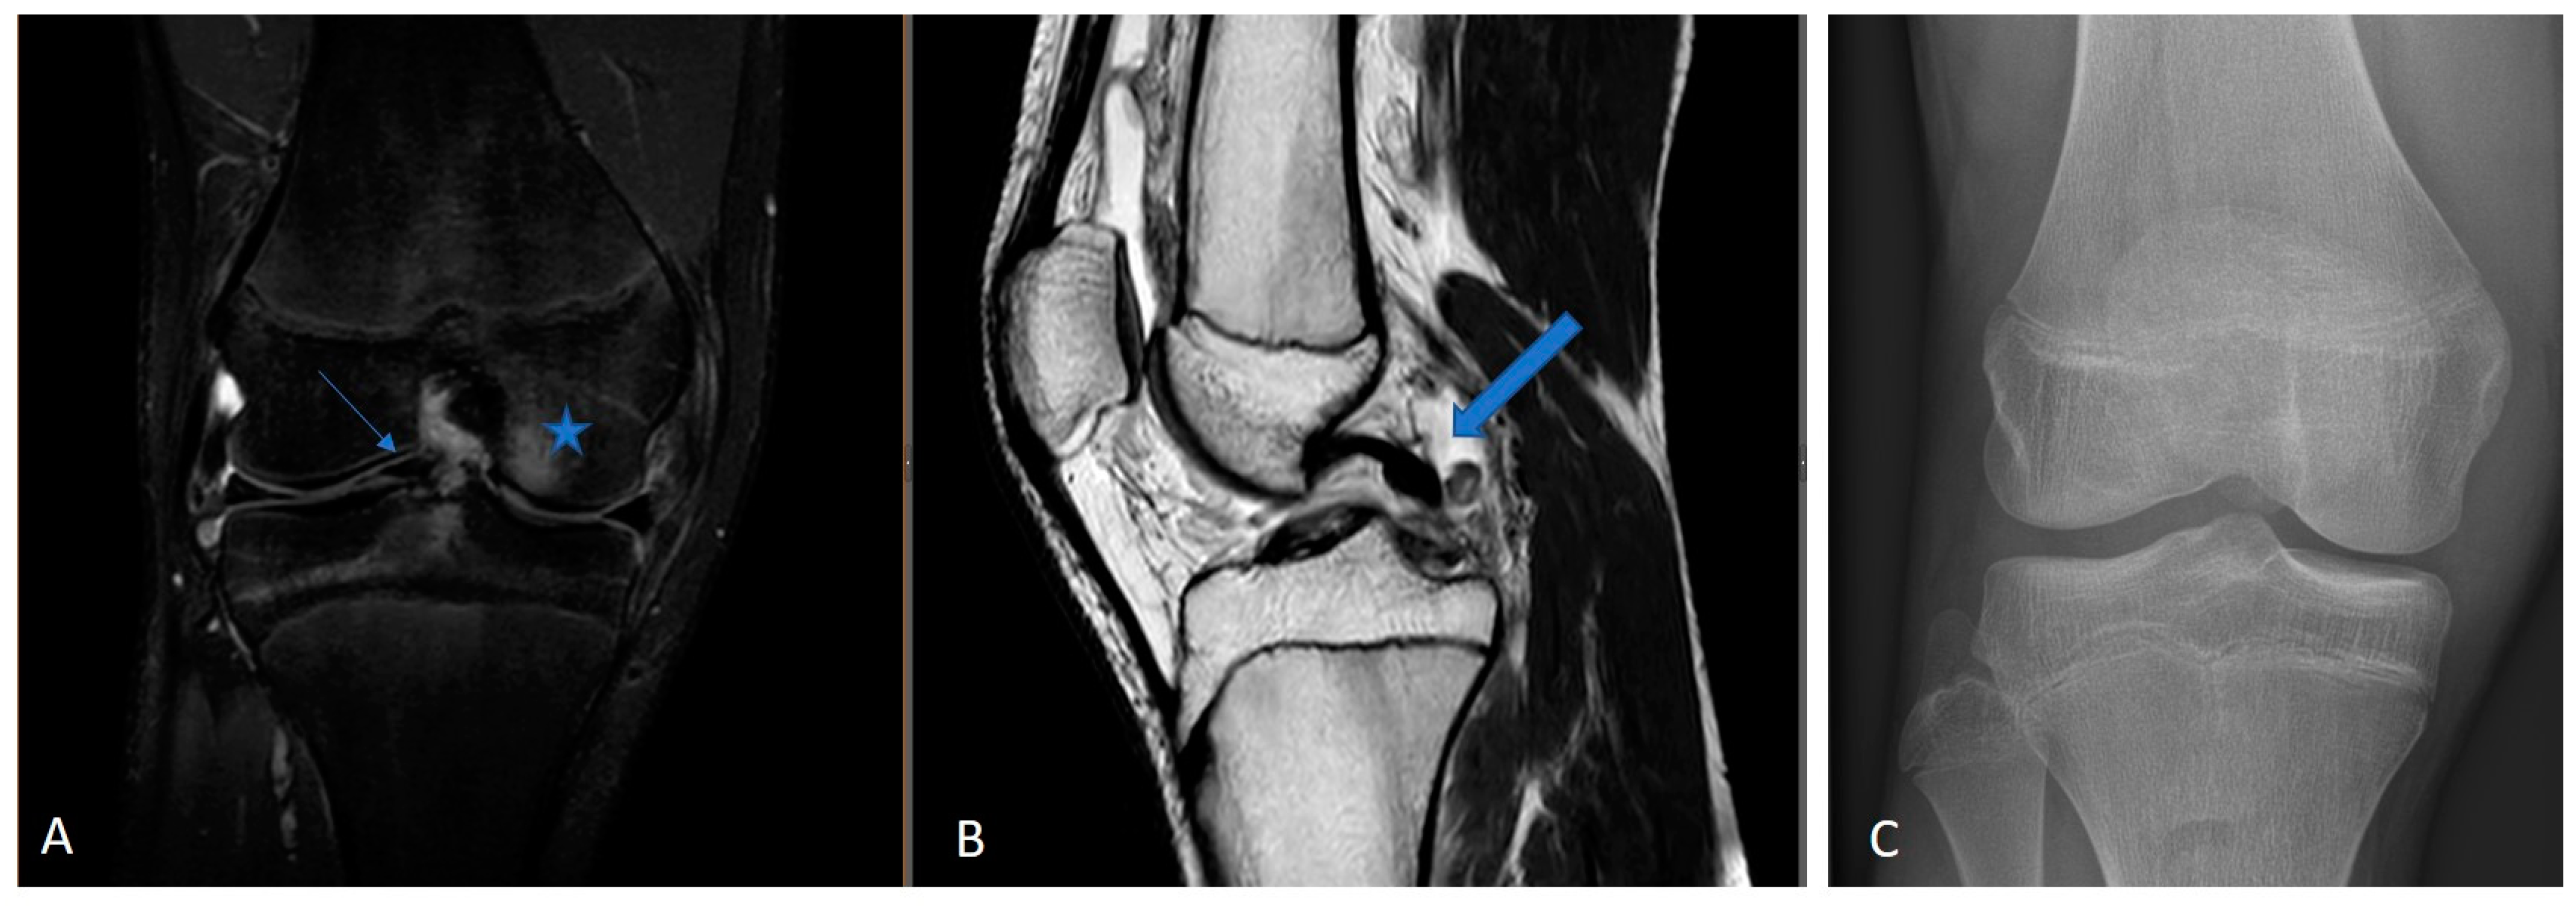

This retrospective study included skeletally immature patients presenting with full-thickness ACL tears, confirmed by MRI and intraoperative evaluation. Patient examples are shown in Figure 1.

Figure 1.

Example of a 3.0 Tesla knee MRI: (A) coronal PD tse fs, (B) sagittal T2 tse, and (C) conventional X-ray in AP view of 14-year-old male patient with open physis and acute ACL rupture. PD tse fs (proton density-weighted turbo spin echo sequence with fat saturation), T2 tse (T2-weighted turbo spin echo sequence), ap (anterior–posterior); large arrow is ACL rupture; star is bone marrow edema.